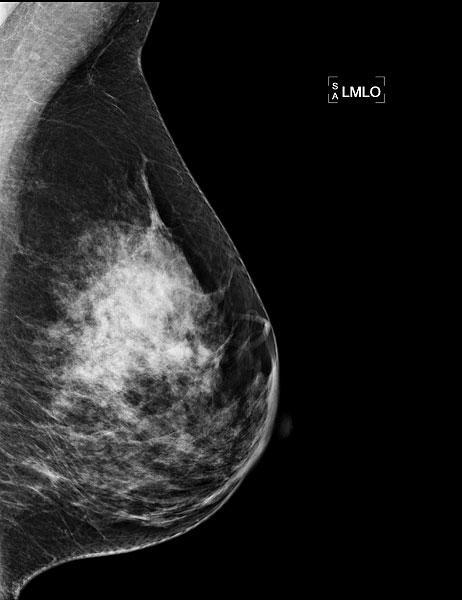

Die Basis der Brustdiagnostik ist die Mammographie, die Methode zur Früherkennung von Brustkrebs. Die Mammographie wird mit einem speziellen Röntgen-Gerät durchgeführt. Die Brust wird zwischen zwei Plexiglasplatten gelegt und leicht zusammengepresst, um eine möglichst dünne Schicht mit wenig Überlagerung zu erhalten. Die Aufnahme dauert nur einen Sekundenbruchteil und ist nicht spürbar. Jede Brust wird in zwei verschiedenen Ebenen geröntgt.